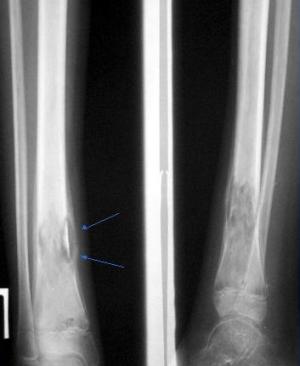

- Острый серозный флюс развивается за 1-3 дня, мягкие ткани отекают. Локализация флюса зависит от расположения больного зуба, а величина зависит от сосудов надкостницы. Развивается серозный вид в результате ушибов и переломов. Воспаление быстро стихает и приводит в ряде случаев к образованию фиброзных наростов и отложению кальциевых солей. Может образовываться новая костная ткань — оссифицирующий периостит.

- Острый гнойный флюс выявляет себя острыми пульсирующими болями, иррадирующими в глаз, висок, ухо. Слизистая оболочка краснеет и отекает, а также повышается температура до 38,5оС. В процессе развития гнойного содержимого симптомы периостита только усиливаются. Причинами заболевания также могут быть открытые переломы на других костях, а не только челюстной. Гнойное воспаление может случиться при варикозном расширении вен, трофических язвах голени, слоновости, тромбофлебитах. Кроме того, причинами острых и хронических воспалений надкостниц голени могут стать разрывы сухожилий, аллергические воспаления, ревматизм, воздействие токсинов.